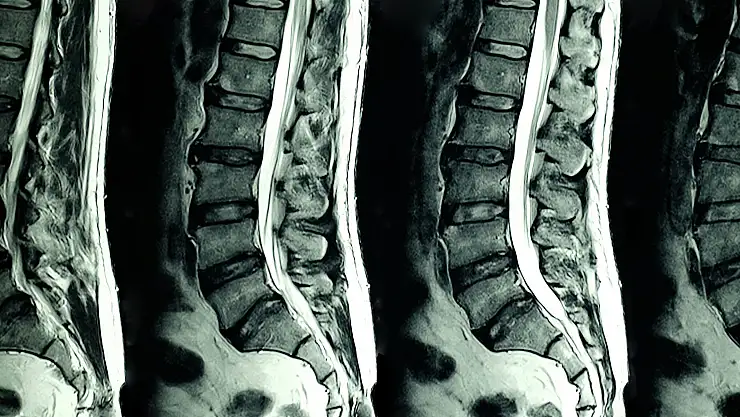

Dejeneratif hastalıkların örnekleri arasında osteoartrit (eklem kireçlenmesi), Alzheimer hastalığı, Parkinson hastalığı, dejeneratif disk hastalığı (omurga disklerinin bozulması), multipl skleroz (MS) ve Huntington hastalığı gibi durumlar bulunmaktadır.

Omurga ağrısı, hareket kısıtlılığı (dejeneratif disk hastalığı)